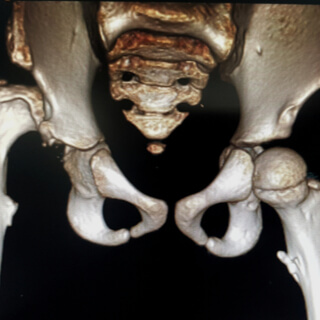

يعد خلع الولادة أو خلع التنسج النمائي المعروف ب (DDH) عبارة عن تطور غير طبيعي لمفصل الورك بحيث تكون الكرة الموجودة في الجزء العلوي من عظم الفخذ غير مستقرة داخل تجويف الورك، وقد تكون أربطة المفصل مشدودوة أو مرتخية.

يعد جهاز خلع الولادة عبارة عن جبيرة ناعمة، ويساعد في إعادة المفصل إلى وضعه الطبيعي، ويساعد أيضًا في تعزيز الشفاء عند الأطفال الذين يعانون من كسر في عظم الفخذ، كما أن الأربطة أو الأنسجة الليفية تساعد على تثبيت رأس الفخذ في مكانه.

ومن خلال ارتداء الجهاز ورفع الساقين وثنيهما فإن الجهاز يساعد رؤوس الفخد على العودة للتجويف الصحيح مما يشجع النمو والتطور الطبيعي للطفل دون الحاجة لتدخل جراحي أو إجراء طبي.